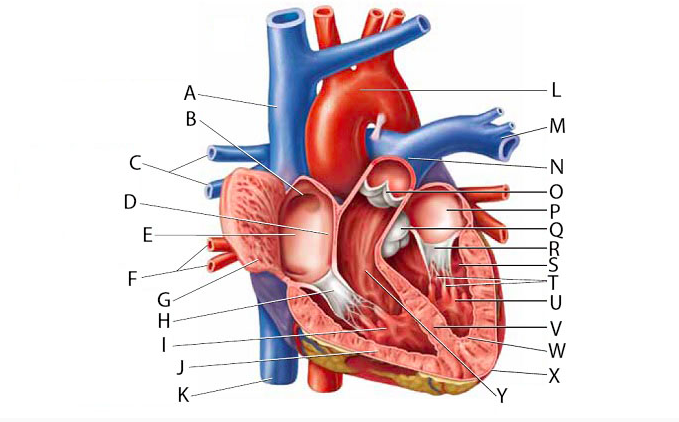

Anterior interventricular valve

Aortic Valve (=left semilunar)

Apex (of the heart)

Chordae tendineae

Coronary sinus

Endocardium

Epicardium

Left atrioventricular (=bicuspid, =mitral) valve

Left/right atrium

Left/right auricle

Left/right coronary artery

left/right ventricle

Myocardium

Papillary muscles

Pectinate muscles

Pericardial sac (=fibrous pericardium)

Pulmonary valve (=right semilunar)

Right atrioventricular (=tricuspid) valve

Superior/inferior vena cava